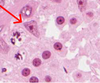

Early spermatids

Primary spermatocytes

Sertoli

Sertoli cell

Spermatogonia

Early spermatids

Primary spermatocytes

Sertoli

Sertoli cell

Spermatogonia